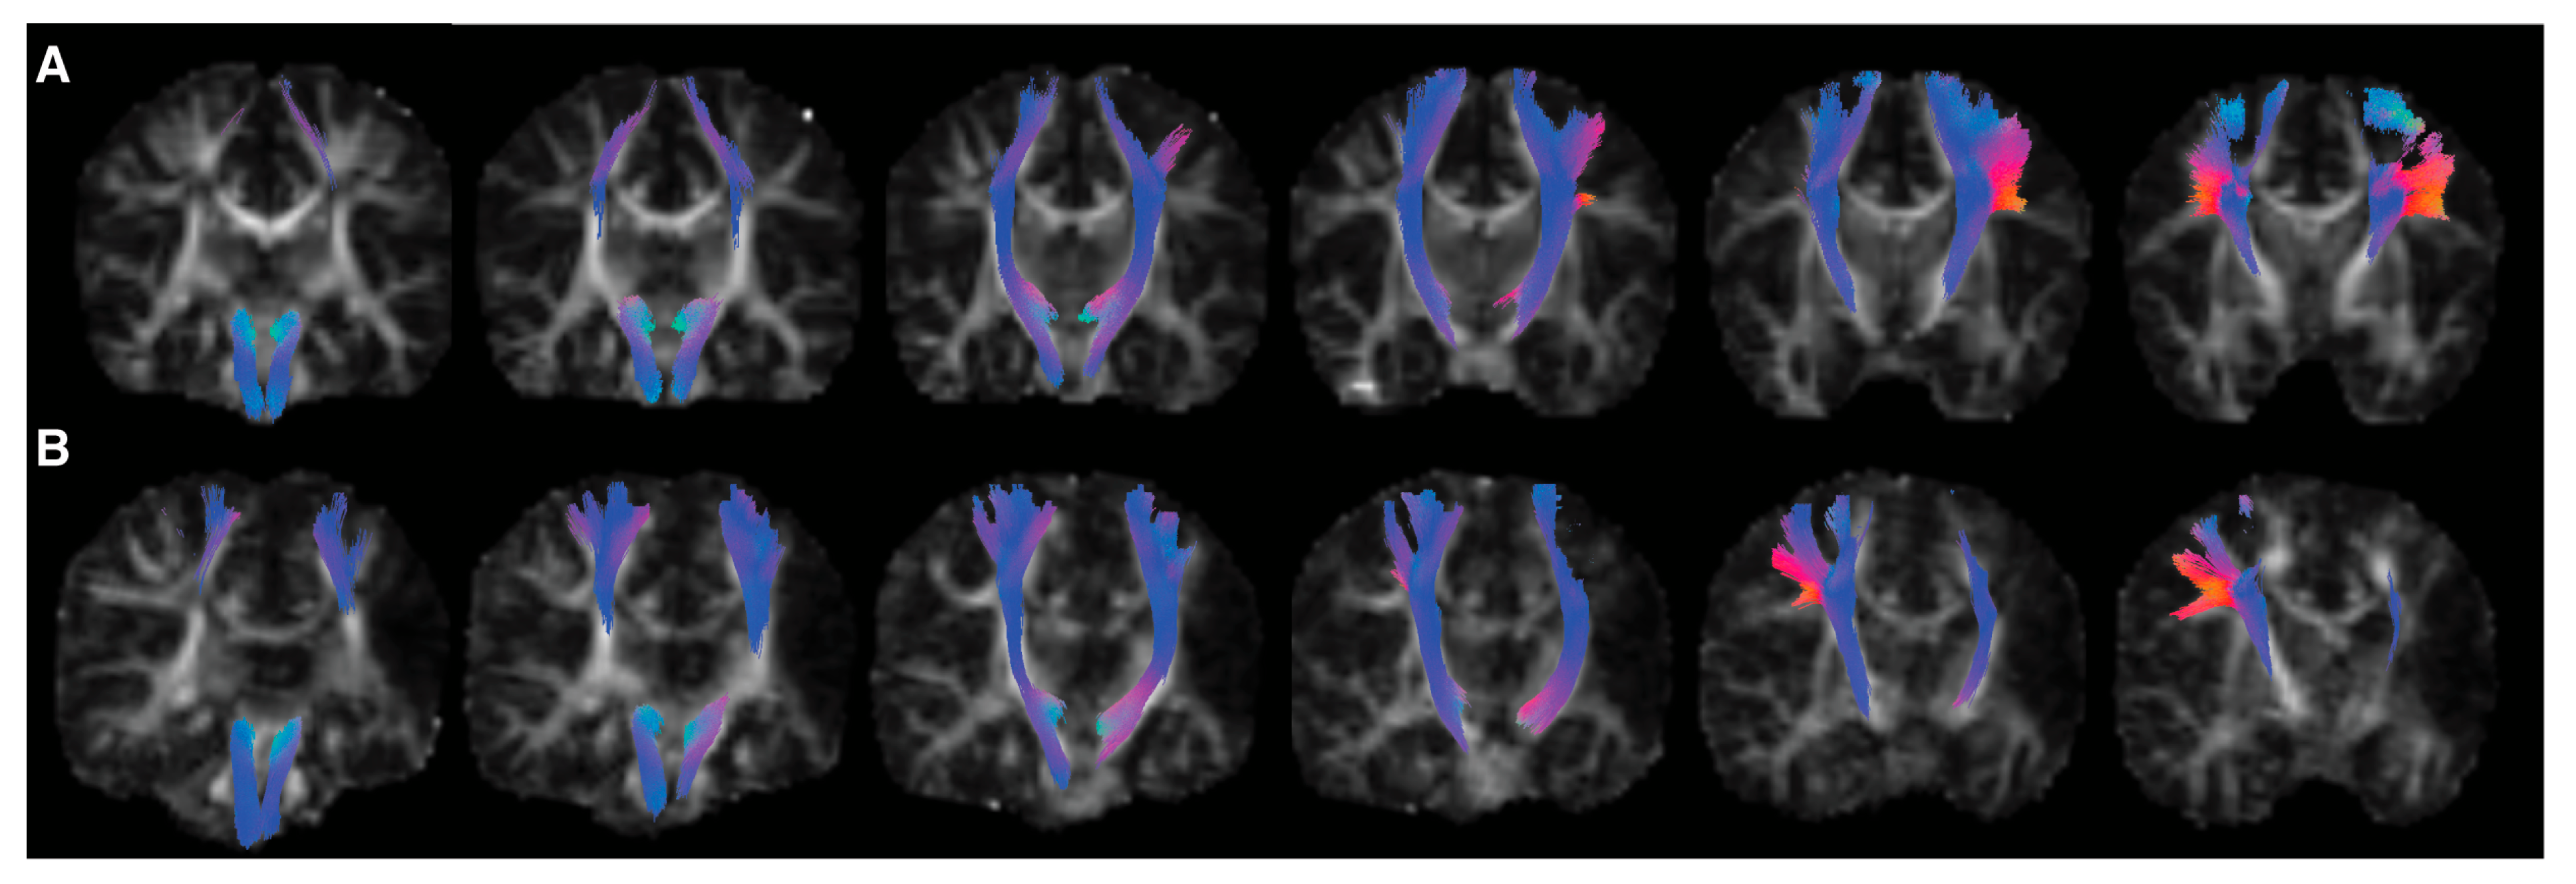

2.4.2. Tractography

3.1. Tractography

3.2. Tract-Based Spatial Statistics